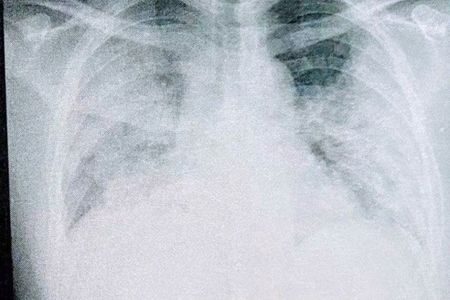

「もう助からない」専門家ですらそのように見えたほど真っ白になった肺。これが37歳のコロナ患者が味わった現実だ(写真:取材者提供/東洋経済オンライン)

[写真 1/7枚目] 「もう助からない」専門家ですらそのように見えたほど真っ白になった肺。これが37歳のコロナ患者が味わった現実だ(写真:取材者提供/東洋経済オンライン)